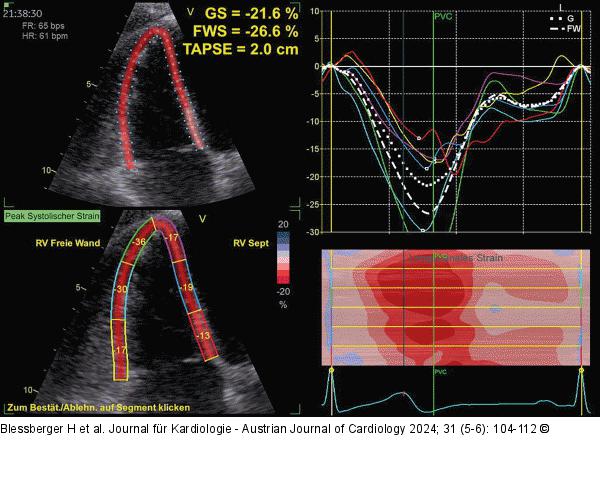

Abbildung 9: Echo Links: Auf den rechten Ventrikel fokussierter apikaler 4-Kammer-Blick. ROI im Bereich des rechten Ventrikels (freie Wand und interventrikuläres Septum). Angezeigt werden links oben der globale Strain des rechten Ventrikels (–21,6 %), der globale rechtsventrikuläre Strain der freien Wand (–26,6 %) sowie automatisch auch die TAPSE (20 mm). Links unten werden die segmentalen rechtsventrikulären Strainwerte angezeigt. Rechts oben: Die Strainkurven aller rechtsventrikulärer Segmente (synchroner Kontraktionsablauf). |

Links: Auf den rechten Ventrikel fokussierter apikaler 4-Kammer-Blick. ROI im Bereich des rechten Ventrikels (freie Wand und interventrikuläres Septum). Angezeigt werden links oben der globale Strain des rechten Ventrikels (–21,6 %), der globale rechtsventrikuläre Strain der freien Wand (–26,6 %) sowie automatisch auch die TAPSE (20 mm). Links unten werden die segmentalen rechtsventrikulären Strainwerte angezeigt. Rechts oben: Die Strainkurven aller rechtsventrikulärer Segmente (synchroner Kontraktionsablauf). |